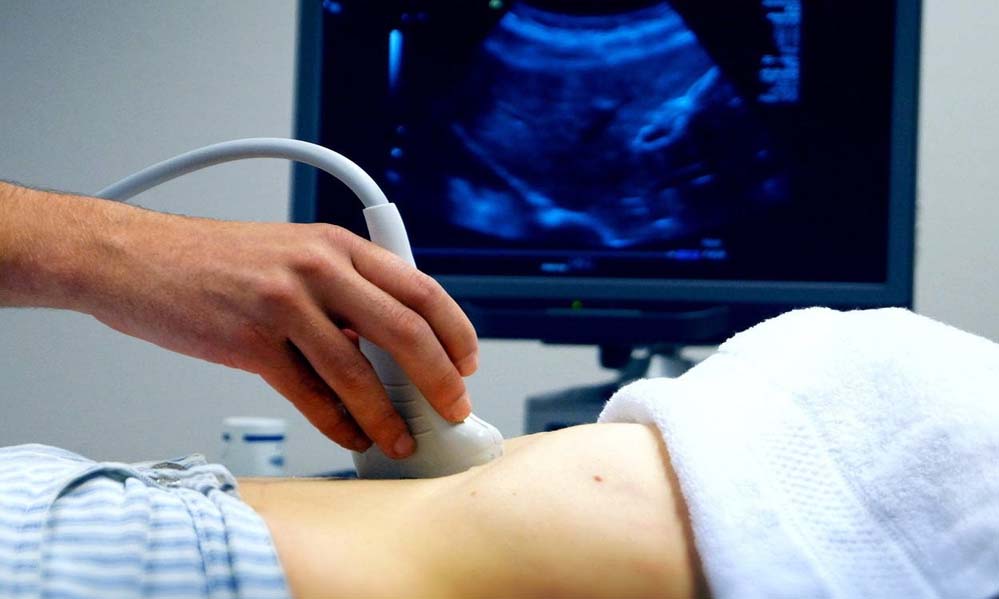

विशेषज्ञों के अनुसार, गर्भपात एक वैज्ञानिक प्रक्रिया है, जिसे तय समय-सीमा और डॉक्टर की निगरानी में ही किया जाना चाहिए। सोनोग्राफी और जरूरी जांच के बाद ही दवा दी जानी चाहिए। डॉक्टरों का कहना है कि अधूरे गर्भपात के कारण अत्यधिक खून बहने से महिलाओं का ब्लड प्रेशर गिर जाता है और शरीर का सिस्टम फेल होने लगता है। कई मामलों में जान तक चली जाती है।